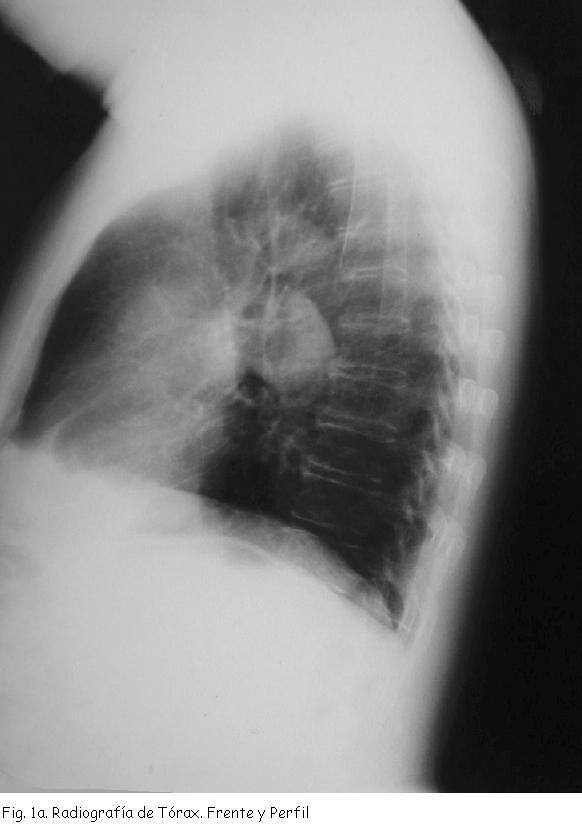

Radiografía de tórax muestra opacidad redondeada de contornos bien delimitados a nivel hiliar izquierdo.(Figura 1a, 1b)